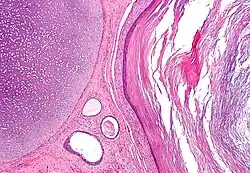

A mature teratoma is a grade 0 teratoma. They are highly variable in form and histology, and may be solid, cystic, or a combination of the two. A mature teratoma often contains several different types of tissue such as skin, muscle, and bone. Skin may surround a cyst and grow abundant hair . Mature teratomas generally are benign, with 0.17–2% of mature cystic teratomas becoming malignant.[18]

Dermoid cyst

A dermoid cyst is a mature cystic teratoma containing hair (sometimes very abundant) and other structures characteristic of normal skin and other tissues derived from the ectoderm. The term is most often applied to teratoma on the skull sutures and in the ovaries of females.